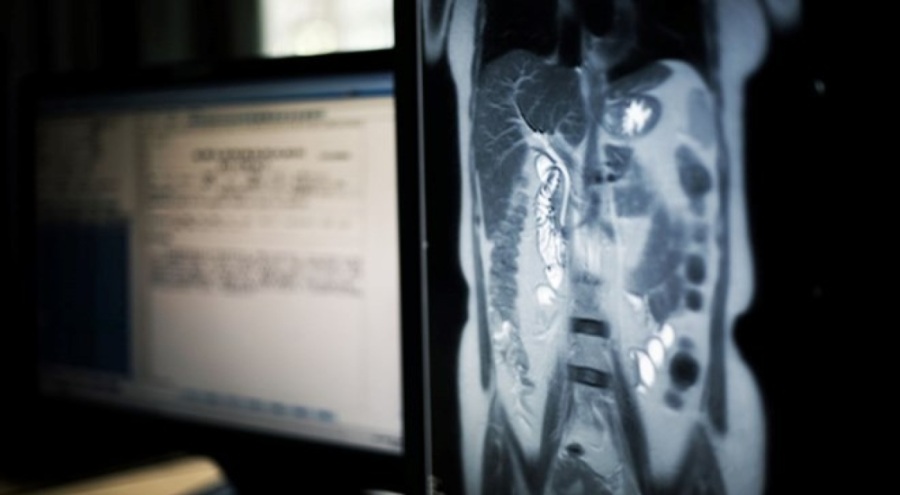

Yerli halkın üyeleri iddia beyanında, "Klostrofobik MRI odasında nefesini tutarak ve etrafındaki yüksek seslerden sinerek uzanırken, MRI taramaları bilgisi veya rızası olmadan vücuduyla ilgili özel bilgileri açığa çıkaran veriler üretti. Tek bir nedenden ötürü seçilmişti; etnik kimliği." ifadelerine yer verdi.